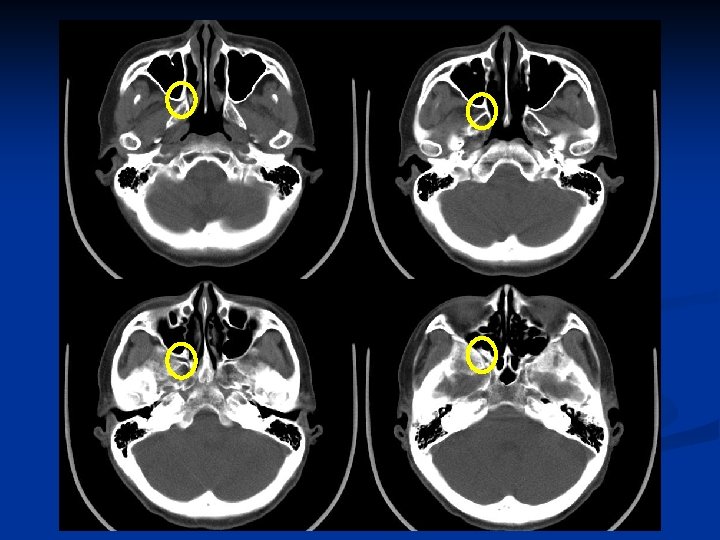

Pterygopalatine fossa (PPF)

Foramen ovale-CN V 3 Foramen lacerum-ICA Foramen lacerum Foramen ovale